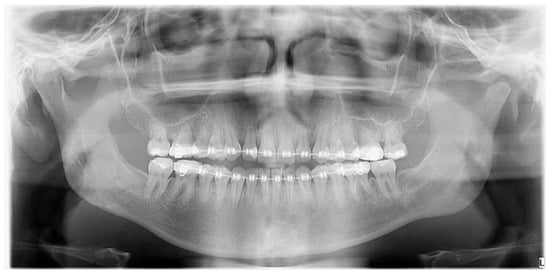

Figure 7.

The final outcome for each asymmetry treatment should be focused on restoring facial balance, oval, symmetry, and improved bite. In the presented figure, both the anterior open bite and mandibular shift towards the right healthy side were successfully achieved in one surgery, meeting the patient’s expectations. Since UCH cases are not that common and can be easily misdiagnosed as normal bone asymmetries, laterognathia, or similar cases, it is quite important to plan each surgery step-by-step in CT/CBCT and compare the 3D dimensions of each mandibular body, ramus, and condyle. Each case of atypical asymmetry should be scheduled for a SCPECT-CT evaluation and a condylectomy procedure when the growth is present (min > 10%), active during a period of time, and not decreasing in time. Some authors reported that UCH can be found in patients between 12 and 50 years of age, depending on the scope of pathological abnormal growth and its occurrence in time (rapid growth, slow progression in time, growth cessation) [1,2,3,4,5]. Sometimes, a condylectomy is sufficient enough to restore mandibular balance when skeletal disproportions are not large enough. If the dento-alveolar discrepancies are severe, then the classic osteotomy protocol of orthognathic surgery should be used after patient orthodontic preparation (consisting of Lefort I maxillary osteotomy, BSSO of the mandible, and chin genioplasty). Rarely, when a balanced profile and proper bone proportions are not met, a third surgery focused on facial contouring and re-balancing is necessary (marginectomies, ostectomies, chin wing or others, bone grafting, or implants). In most cases, each clinician should deal with each patient individually because the scope of growth, bone changes, present skeletal malocclusion, bone over-growths, and related changes to both the skeletal profile and even maxillary cant deviation might necessitate a different protocol in each case.